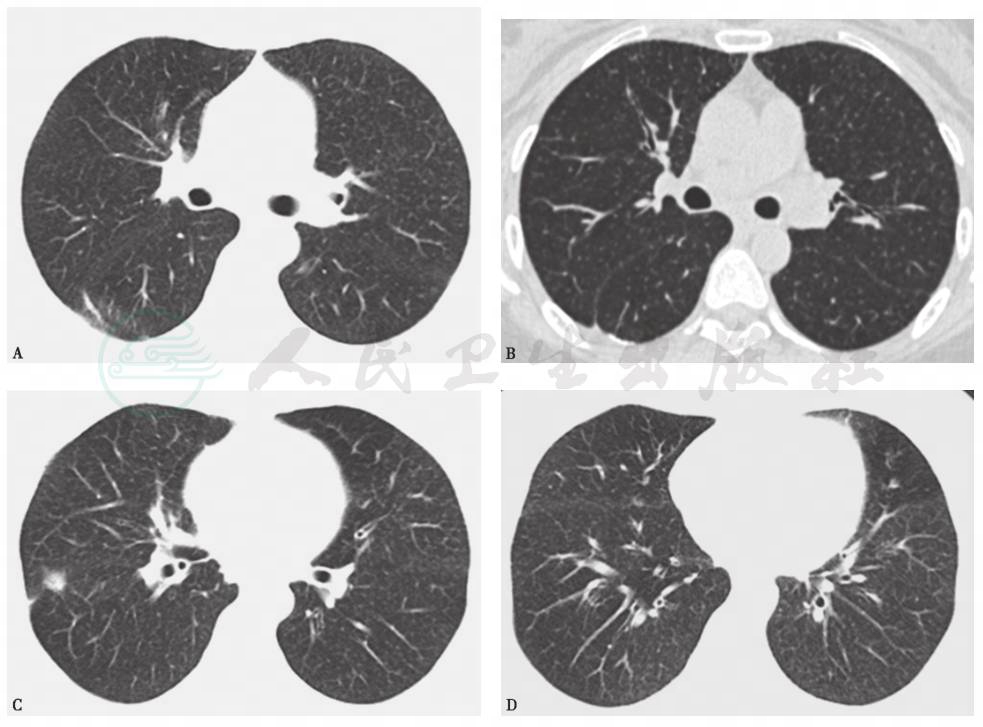

胸部CT:可见双肺纹理增多,有散在粟粒影,支气管柱状扩张,以下叶为主,伴有树芽征;双下肺小叶间隔增厚;纵隔内2R、4L、4R及5区可见肿大淋巴结;双侧胸膜未见异常(图5)。

图5 胸部CT表现

胸部CT可见散在粟粒影,支气管柱状扩张,以下叶为主,伴有树芽征和小叶间隔增厚(A、C、D);纵隔内4L、4R及5区可见肿大淋巴结(B)